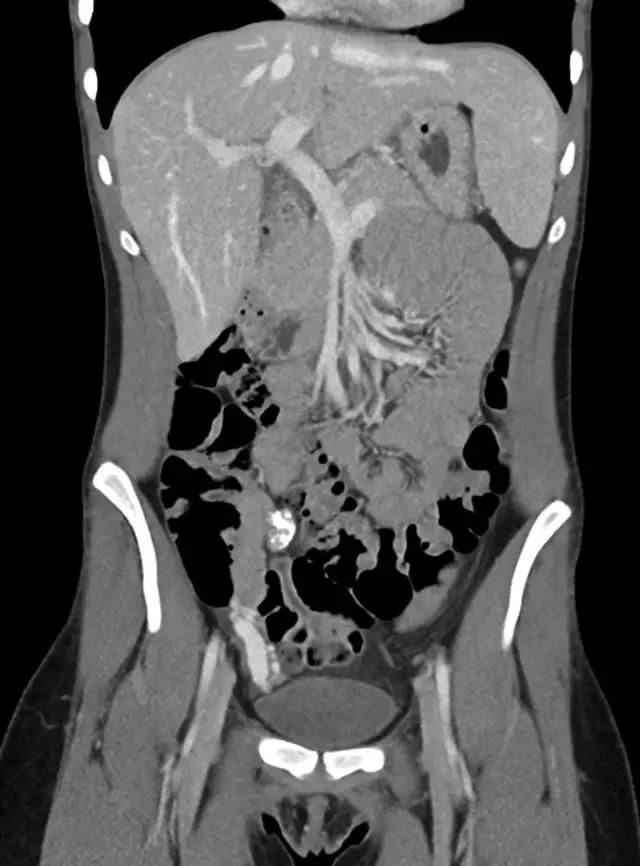

腹部超声未显示:阑尾异常及右下腹感染或积液征象。腹部 CT 见盆腔少量游离液体及阑尾钙化表现(图 1)。

图 1 腹部 CT 示右下腹钙化灶